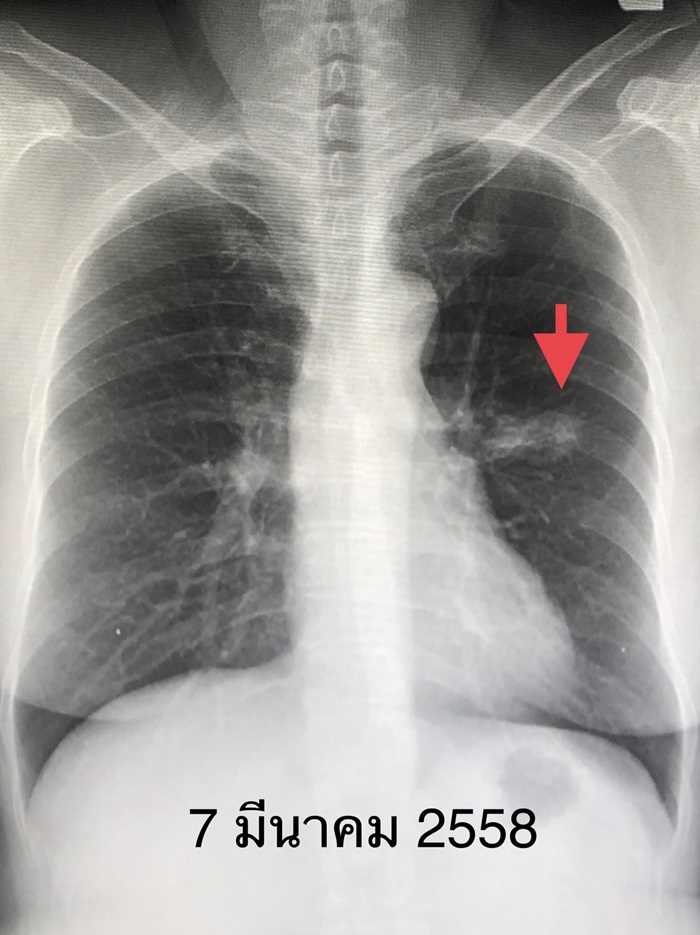

ผู้ป่วยหญิงอายุ 65 ปี เมื่อ 7 ปีก่อน ตรวจร่างกายประจำปี และเอกซเรย์ปอดทุกปี พบก้อนเล็ก ๆ ที่ปอดข้างซ้ายด้านบน ผ่านไป 1 ปี ก้อนนี้โตขึ้น (ดูรูป) จึงมาปรึกษา ผู้ป่วยไม่มีอาการ ไม่ไอ ไม่มีไข้ ไม่เหนื่อย ไม่เจ็บหน้าอก น้ำหนักไม่ลด เป็นโรคความดันโลหิตสูง ไม่สูบบุหรี่ แต่จุดธูป 20 ดอกในที่ทำงานทุกวันพฤหัสต่อเนื่อง 6 ปี ทำคอมพิวเตอร์สแกนปอดพบก้อนที่ปอดข้างซ้ายด้านบน ค่ามะเร็งในเลือดปกติ ทำ PET scan สงสัยเนื้องอกเป็นมะเร็งปอด ไม่กระจายไปอวัยวะอื่น ส่องกล้องเข้าไปดูในหลอดลม ไม่พบอะไรผิดปกติ

ได้ทำการผ่าตัดปอดโดยวิธีส่องกล้องเมื่อวันที่ 7 มีนาคม 2558 ตัดปอดกลีบบนข้างซ้ายออก และตัดชิ้นเนื้อจากต่อมน้ำเหลืองที่ขั้วปอด และรอบ ๆ เนื้องอก ผลพยาธิวิทยาเป็นมะเร็งปอดขนาด 4 เซนติเมตร ชนิด adenocarcinoma ยังไม่กระจายเข้าต่อมน้ำเหลือง